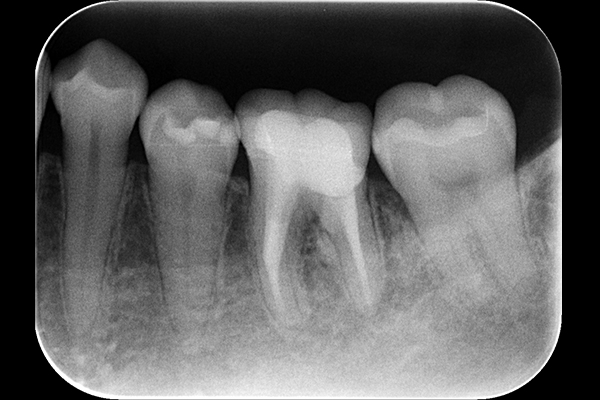

7.根管充填をした時のレントゲン

根管充填をした時のレントゲン写真です。

C型の根を詰めると、この様に帯状に詰め物が確認できます。